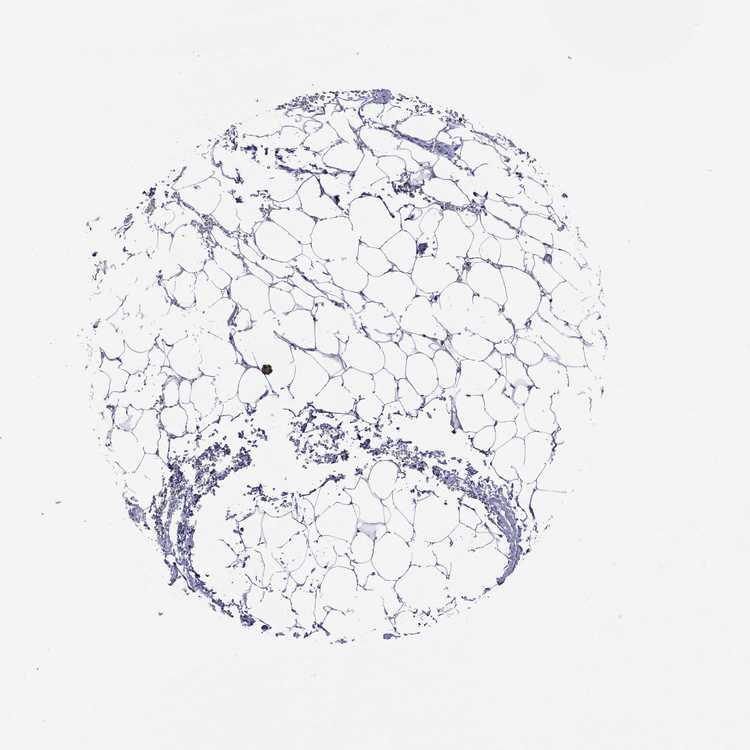

SOFT TISSUE 2 - Antibody stainingi

Antibody staining in the annotated cell types in the current human tissue is reported as not detected, low, medium, or high, based on conventional immunohistochemistry profiling in selected tissues. This score is based on the combination of the staining intensity and fraction of stained cells.

Each image is clickable and will lead to virtual microscopy that enables deeper exploration of all samples and also displays staining intensity scores, fraction scores and subcellular localization as well as patient and tissue information for each sample.

Antibody HPA015103

Chondrocytes Not detected

Fibroblasts Not detected

Peripheral nerve Not detected